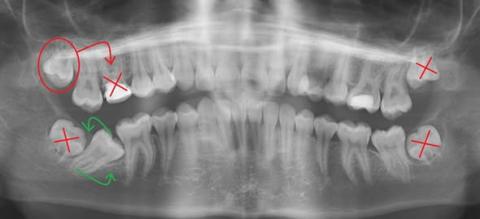

Impacted Wisdom Teeth (18, 28, 38, 48)

All four third molars show full impaction.

18 (upper left) – Vertically impacted, pushing against tooth 17.

28 (upper left) – Fully impacted; removal recommended.

38 (lower left) – Horizontally impacted, pushing forward into 37.

48 (lower right) – Also horizontally impacted.

Tooth 47 – Impacted Premolar/Molar

Tooth 47 is impacted and not in its proper occlusal position.

It’s tilted and trapped under the distal root of 46.

Tooth 16 – Large Restoration With Poor Prognosis

The large filling compromises tooth strength:

Decision: Extract 16 and replace it using transplanted tooth 18 — a rare but effective alternative when executed by a skilled oral surgeon.